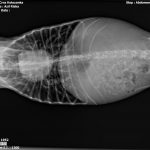

Die Röntgenaufnahmen zeigten, dass ihr Herz vergrößert ist und die Lunge bereits betroffen.

Ein Test bestätigte den Verdacht auf Herzwürmer.

Sweety ist seit sie ins Asyl gekommen ist, unter Therapie.

Die Herzwurmbehandlung ist zwar unkompliziert, aber immer sehr langwierig aufgrund der Lebenszyklen der Würmer.

Gerade bei starkem Befall muss man vorsichtig vorgehen.

Sweety atmet etwas schwer und auch ihre Leberwerte waren eine Katastrophe, erholen sich aber langsam.